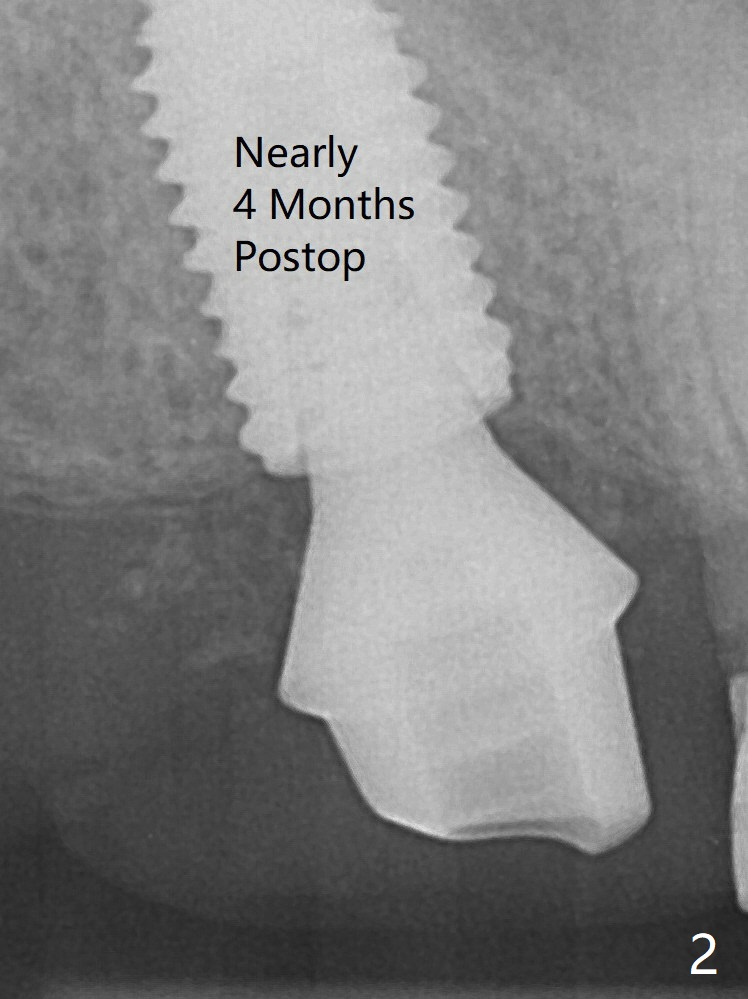

There is small scale of break of the sinus floor (Fig.1 arrowheads) when the implant is placed. No treatment is rendered for the mucocele. The implant heals without tenderness over the anterior sinus wall nearly 4 months postop (Fig.2), but the abutment is loose with unhealthy gingival cuff. It is difficult to reseat the abutment, probably due to contact with the mesial crest. A 6.8x7 mm healing abutment is placed. A 5.2x4(4) mm cemented abutment is placed before impression. A crown is cemented 6 months postop (Fig.3); there is no gap between the abutment and implant, as compared to Fig.1,2 (+ gap). In fact the abutment is incompletely seated (Fig.5: <). Bone profile drill should be used to trim the mesial crest before reseating crown/abutment.